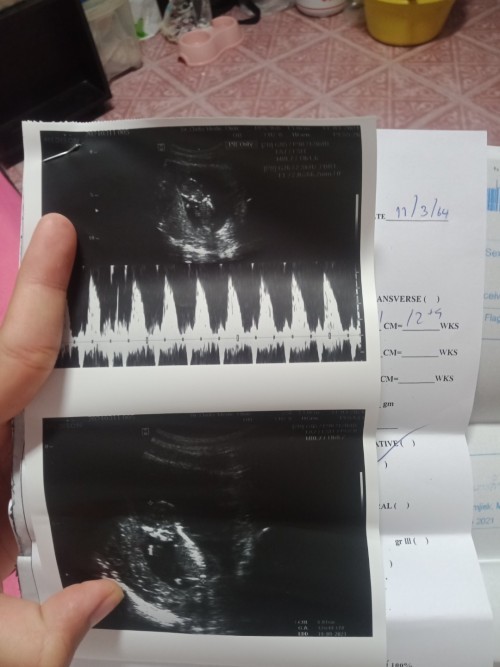

5 สัปดาห์ 6 วัน หัวใจยังไม่เต้นปกติมั้ย?

หลังจากใช้ที่ตรวจด้วยตัวเองพบว่าท้องก็เลยไปฝากครรภ์ที่โรงพยาบาล วันนี้หมอนัดตรวจอีกครั้งหลังจาก 1 สัปดาห์ อัลตร้าซาวด์เจอการตั้งครรภ์ตามภาพเลยค่ะ แต่คุณหมอบอกยังไม่เห็นการเต้นของหัวใจเด็ก ให้รอดูภายใน 1 เดือน นัดตรวจอีกทีอีก 2 สัปดาห์ มีโอกาสเป็นท้องลม เริ่มกังวลขึ้นมาเลยค่ะ 🥺 แม่ ๆ ท่านอื่นเห็นหัวใจลูกเต้นตอนไหนกันบ้างคะ มีใครเป็นเหมือนกันบ้าง ขอความคิดเห็นหน่อยค่ะ 🙏

ไปตรวจมาอีกรอบแล้วค่ะย้ายโรงพยาบาล ตอน 6.3 w เห็นทั้งตัวและหัวใจเต้นครบเลย สบายใจขึ้นเยอะ ขอบคุณทุกท่านมากนะคะ 😊🙏